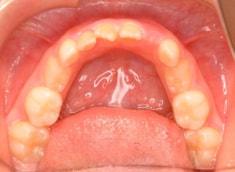

治療前